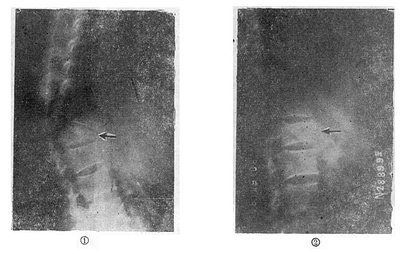

(一)单纯楔状压缩骨折的治疗 轻型的压缩骨折,可以采用保守治疗方法。天津医院骨科发掘我国古代医学遗产,创建了“垫枕背伸肌锻炼法”,是一种可行方法(图73-11)。具体做法为病人仰卧硬板床上,腰部用塔形枕垫起,垫枕正对骨折部位,保持脊柱过伸位。先静卧2~3天,待骨折处出血停止,疼痛减轻及腹气胀反应消退后即开始如图示方法,逐渐加强锻炼。病人卧床3个月,天天坚持锻炼,大部分病人可获得良好的结果(图73-12)。此法的缺点是需较长时间的卧床,且对一些比较严重的压缩骨折,有时复位不够满意。我们经验认为,对于椎体前方压缩50%以上者,特别是青年患者,最好用两根Harrington棍进行手术或Dick法复位固定。可以使骨折解剖复位,而且术后两周即可带石膏围腰或支具下地活动。

垫枕背伸肌锻炼法

图73-11 垫枕背伸肌锻炼法

垫枕背伸锻炼获良好结果

图73-12 垫枕背伸锻炼获良好结果

①骨折初时;②背伸锻炼3个月后